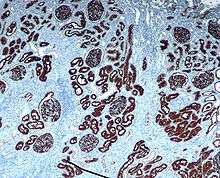

Immunochemistry

CD10 is used in clinical pathology for diagnostic purpose.

In lymphomas and leukemias

- Acute lymphoblastic leukemia (ALL) cells are CD10+.

- Follicular lymphoma (follicle centre cell lymphoma) are CD10+.

- Burkitt Lymphoma cells are CD10+.

- CD10+ diffuse large B cell lymphoma (CD10+ DLBLC)[19]

- Angioimmunoblastic T cell lymphoma (AITL) are CD10+[24][25] and distinguishes AITL from other T cell lymphomas (CD10−)[26]